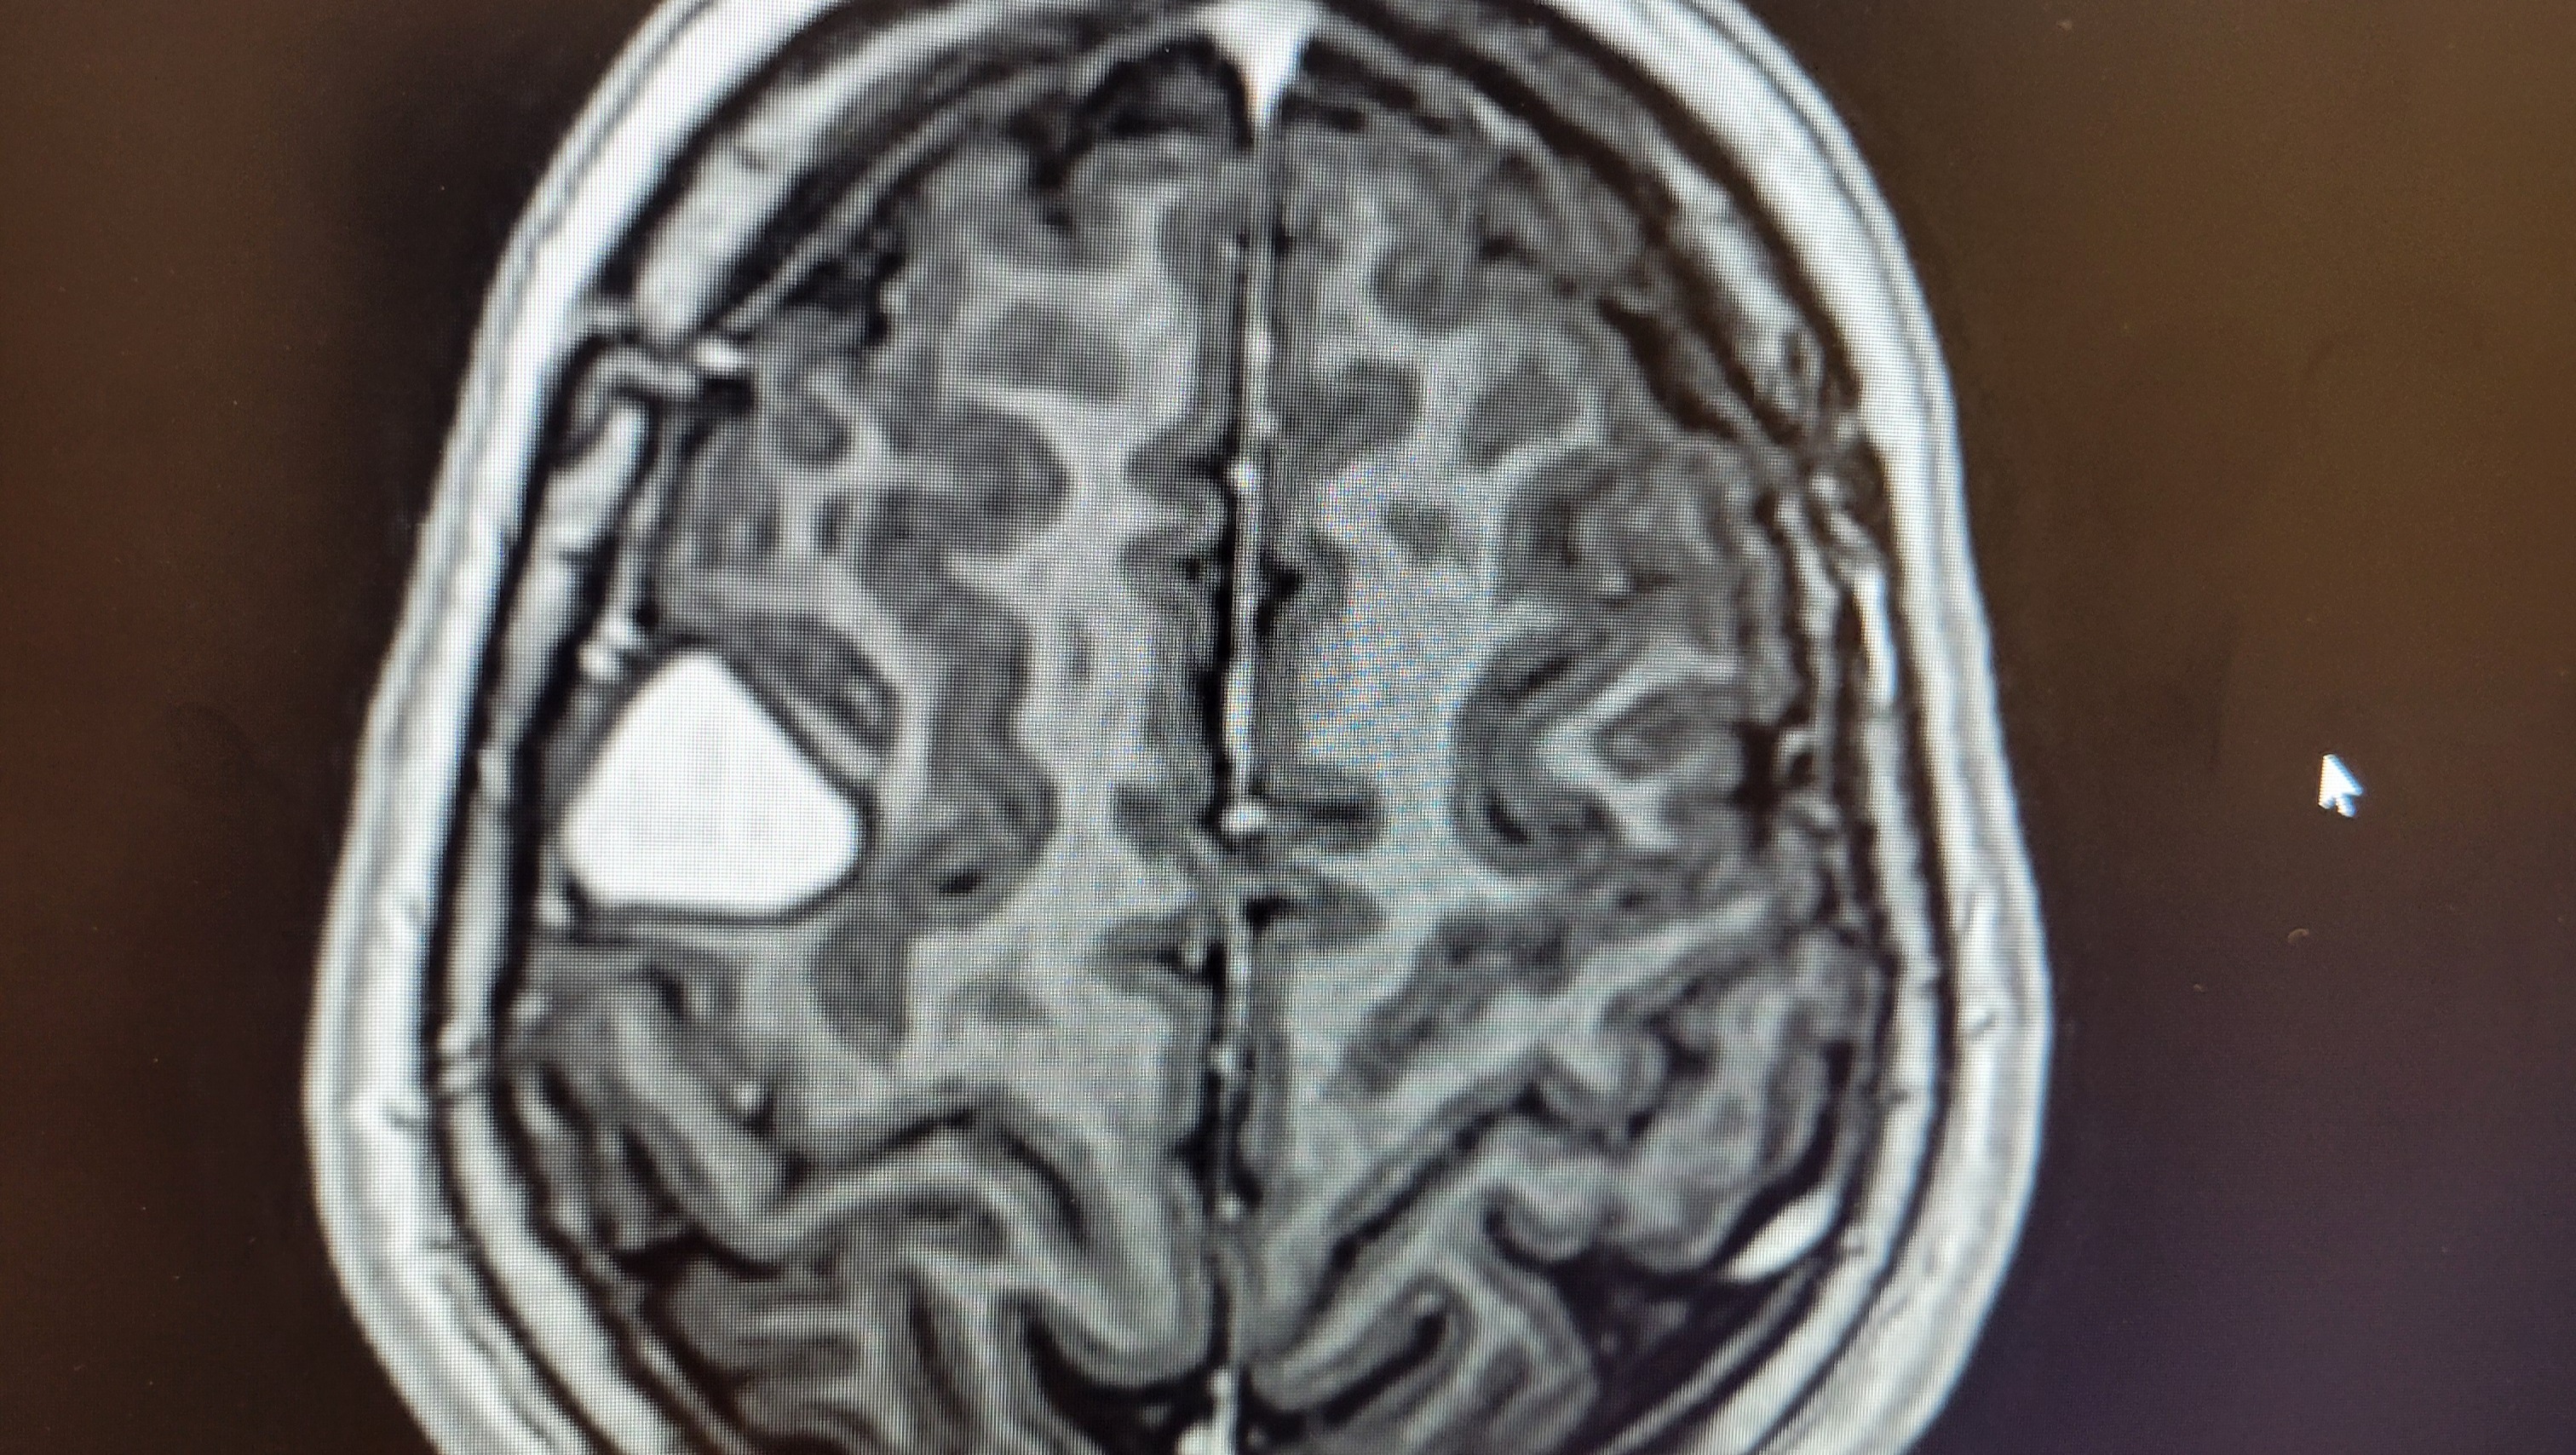

As most don't know, he was diagnosed with a brain tumor not very long ago.